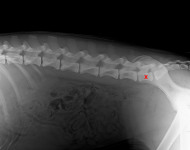

(2) 7 týdnů lat

(2) 7 týdnů lat

(2) typ 3 I

(2) typ 3 I